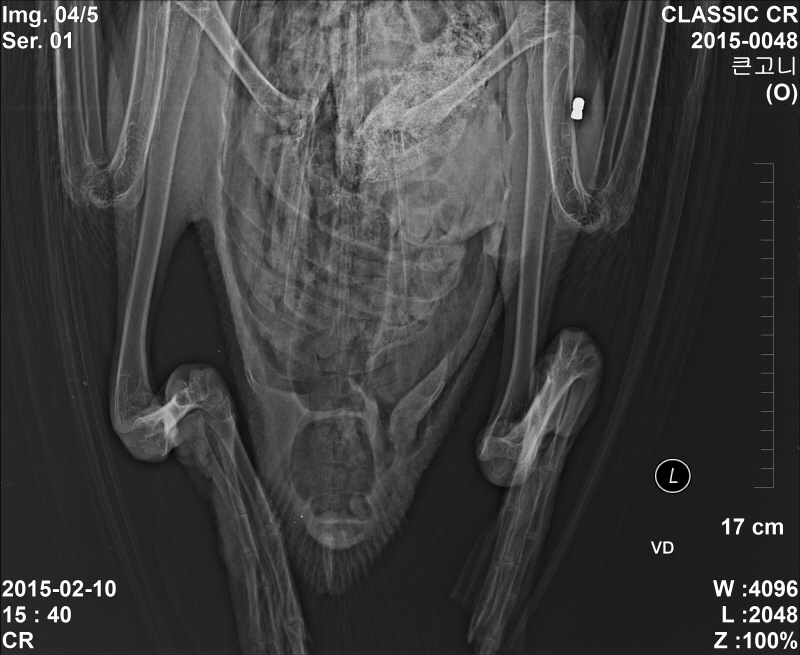

큰고니 공기총에 의한 폐사

철새도래지에 총포에 의한 밀렵이 성행합니다.

저정도 납탄이면 거의 노리고 갓다고 봐야할거 같네요. 보통 저런 탄환은 최소 오리 이상급을 잡을때 쓰는걸로 알고 있는데..대체 잡아서 무엇을 할려고 하는건지...